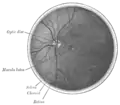

Interior da metade posterior do olho esquerdo.